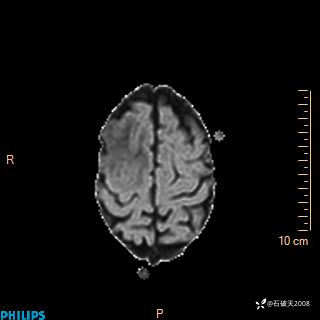

2024.2.21MR

DWI

ADC

增强轴位

增强冠状位

增强矢状位